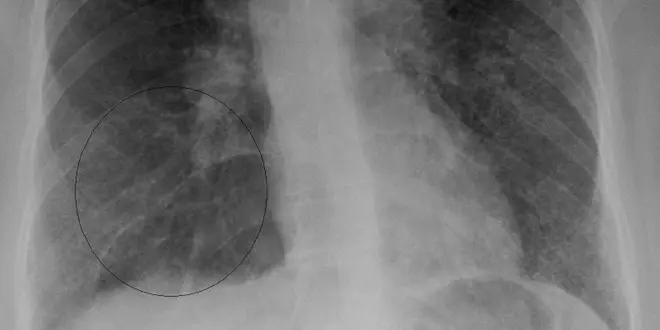

La première forme se manifeste par une fièvre, des douleurs dans les articulations et d'un érythème noueux (en d'autres termes, des bosses douloureuses au niveau des jambes, traduisant l'atteinte du derme, la couche profonde de la peau). Une radiographie du thorax révèle alors des granulomes, en dépit de l'absence de symptôme respiratoire. De simples antalgiques ou anti-inflammatoires soulagent alors les douleurs, et la guérison est observée en quelques semaines (sans séquelles de 8 à 9 fois sur 10). Une récidive est observée dans 5% des cas et, une fois sur 10, la forme aiguë évolue en forme chronique, justifiant une surveillance systématique de deux ans.

La sarcoïdose chronique est plus insidieuse, parfois asymptomatique. Les granulomes peuvent envahir tous les organes mais, dans la grande majorité des cas, c'est la cage thoracique qui est concernée, à la fois au niveau des poumons et des ganglions lymphatiques. Une toux persistant plus de deux semaines et un essoufflement sont alors présents.